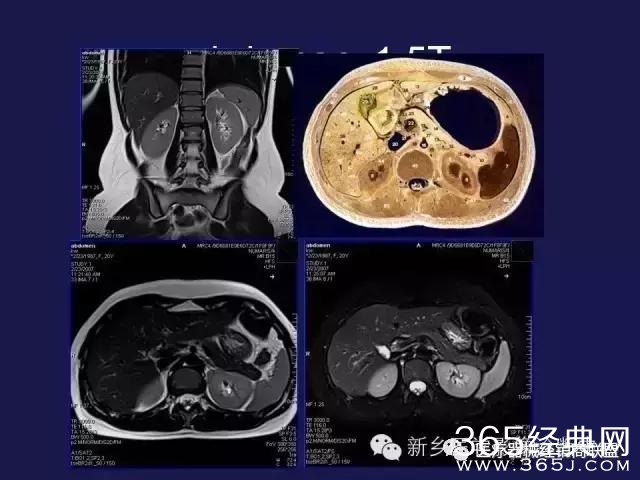

CT、MRI很难?NO,今日我们一起来学习一下如何读CT、MRI!

内行看门道:

整整90张图